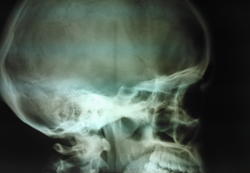

девушка 1996 года рождения направлена на рентгенографию черепа с диагнозом: ВЧГ. беспокоят периодические головные боли. меня насторожила картина турецкого седла. хотелось бы знать мнение коллег, есть ли тут патология или вариант нормы.

спасибо за ссылку, но королюк пишет про мембрану, а в моем случае как мне кажется "обызвествление" вокруг гипофиза, как бы окутывает его. может мне это все кажется. подожду еще мнения коллег, кто что напишет.

Такое ещё называют обызвествлённой диафрагмой седла (вариант нормы). Остальное вроде в норме. Заставляйте р/лаборантов диафрагмировать. Зачем весь череп снимать?

Это гинекологи, если что-то с зачатием, на закрытый тип турецкого седла обращают внимание. А вот каналы диплоических вен расширены. Признаки внутричерепной гипертензии?

Закрытый тип турецкого седла,как вариант нормы.Все тот же Королюк.